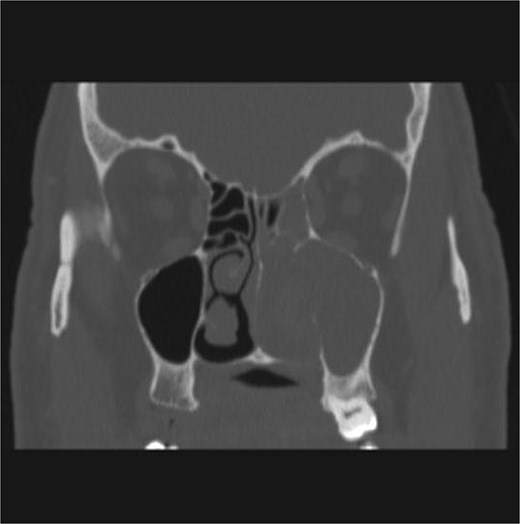

CT showed a heterogeneously enhancing mass completely occluding the left nasal cavity, left ethmoidal, maxillary and frontal sinuses, extending to left pterygopalatine fossa. It is associated with bony erosion of the posterior nasal septum and the left medial maxillary wall (Figs 1 and 2). Findings were suggestive of inverted papilloma vs sinonasal malignancy. Therefore, biopsy was recommended.

Coronal section of CT paranasal sinus with contrast soft tissue window showing the mass occupying the left nasal cavity and extending to maxillary and ethmoidal sinus.